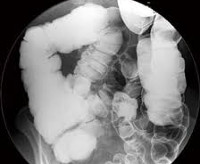

• Рентген толстой кишки. Ирроскопия после перорального введения бариевого контрастного вещества является «золотым» стандартом в диагностике доликоколона. Способ позволяет обнаружить удлиненную ободочную кишку, выявляет значительное замедление прохождения радиокосмических веществ через кишечник.